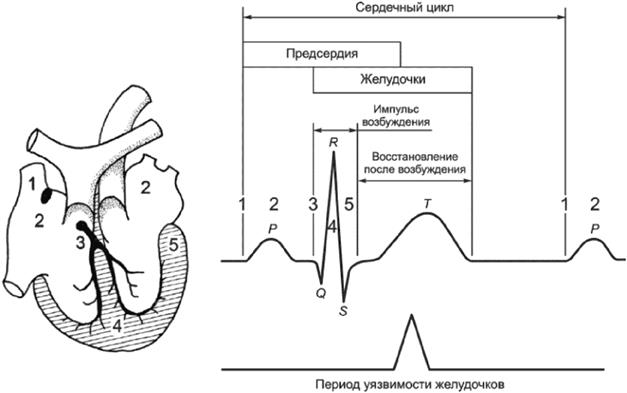

3.2.7 период уязвимости (vulnerable period): Сравнительно небольшая часть сердечного цикла, в течение которой сердечные мышечные волокна находятся в состоянии неоднородной возбудимости, и при воздействии на них электрического тока достаточной силы происходит фибрилляция желудочков.

Примечание - Период уязвимости соответствует первой части зубца T на электрокардиограмме, что составляет приблизительно 10% длительности сердечного цикла.

Порог ФЖ зависит от физиологических характеристик (строение тела, состояние сердца и т.п.), а также от электрических параметров (длительность и путь протекания тока, характеристики тока и т.п.). Описание сердечной деятельности показано на рисунках А.16 и А.17 и в приложении И.

Для синусоидального переменного тока частотой 50/60 Гц происходит заметное снижение порога ФЖ при времени протекании тока более длительности одного сердечного цикла. Причина этого явления состоит в том, что неоднородность возбужденного состояния сердца увеличивается вследствие вызванных током экстрасистол.

Если время воздействия менее 0,1 с, то ФЖ может возникать при токах более 500 мА, а при токах порядка несколько ампер ее возникновение вероятно, только если ток снизится в течение периода уязвимости. При ударах током подобной силы и длительностью более одного периода сердечного цикла может произойти обратимая остановка сердца.

Примечание - Цифры на рисунке соответствуют последовательным стадиям распространения возбуждения.

P - интервал деполяризации предсердий; QRS - интервал деполяризации желудочков; T - интервал реполяризации желудочков

Рисунок А.16 - Период уязвимости желудочков в течение сердечного цикла

P - интервал деполяризации предсердий; ORS - интервал деполяризации желудочков; T - интервал реполяризации желудочков

Рисунок А.17 - Инициирование ФЖ в течение периода уязвимости. Изменения электрокардиограммы (ЭКГ) и кровяного давления